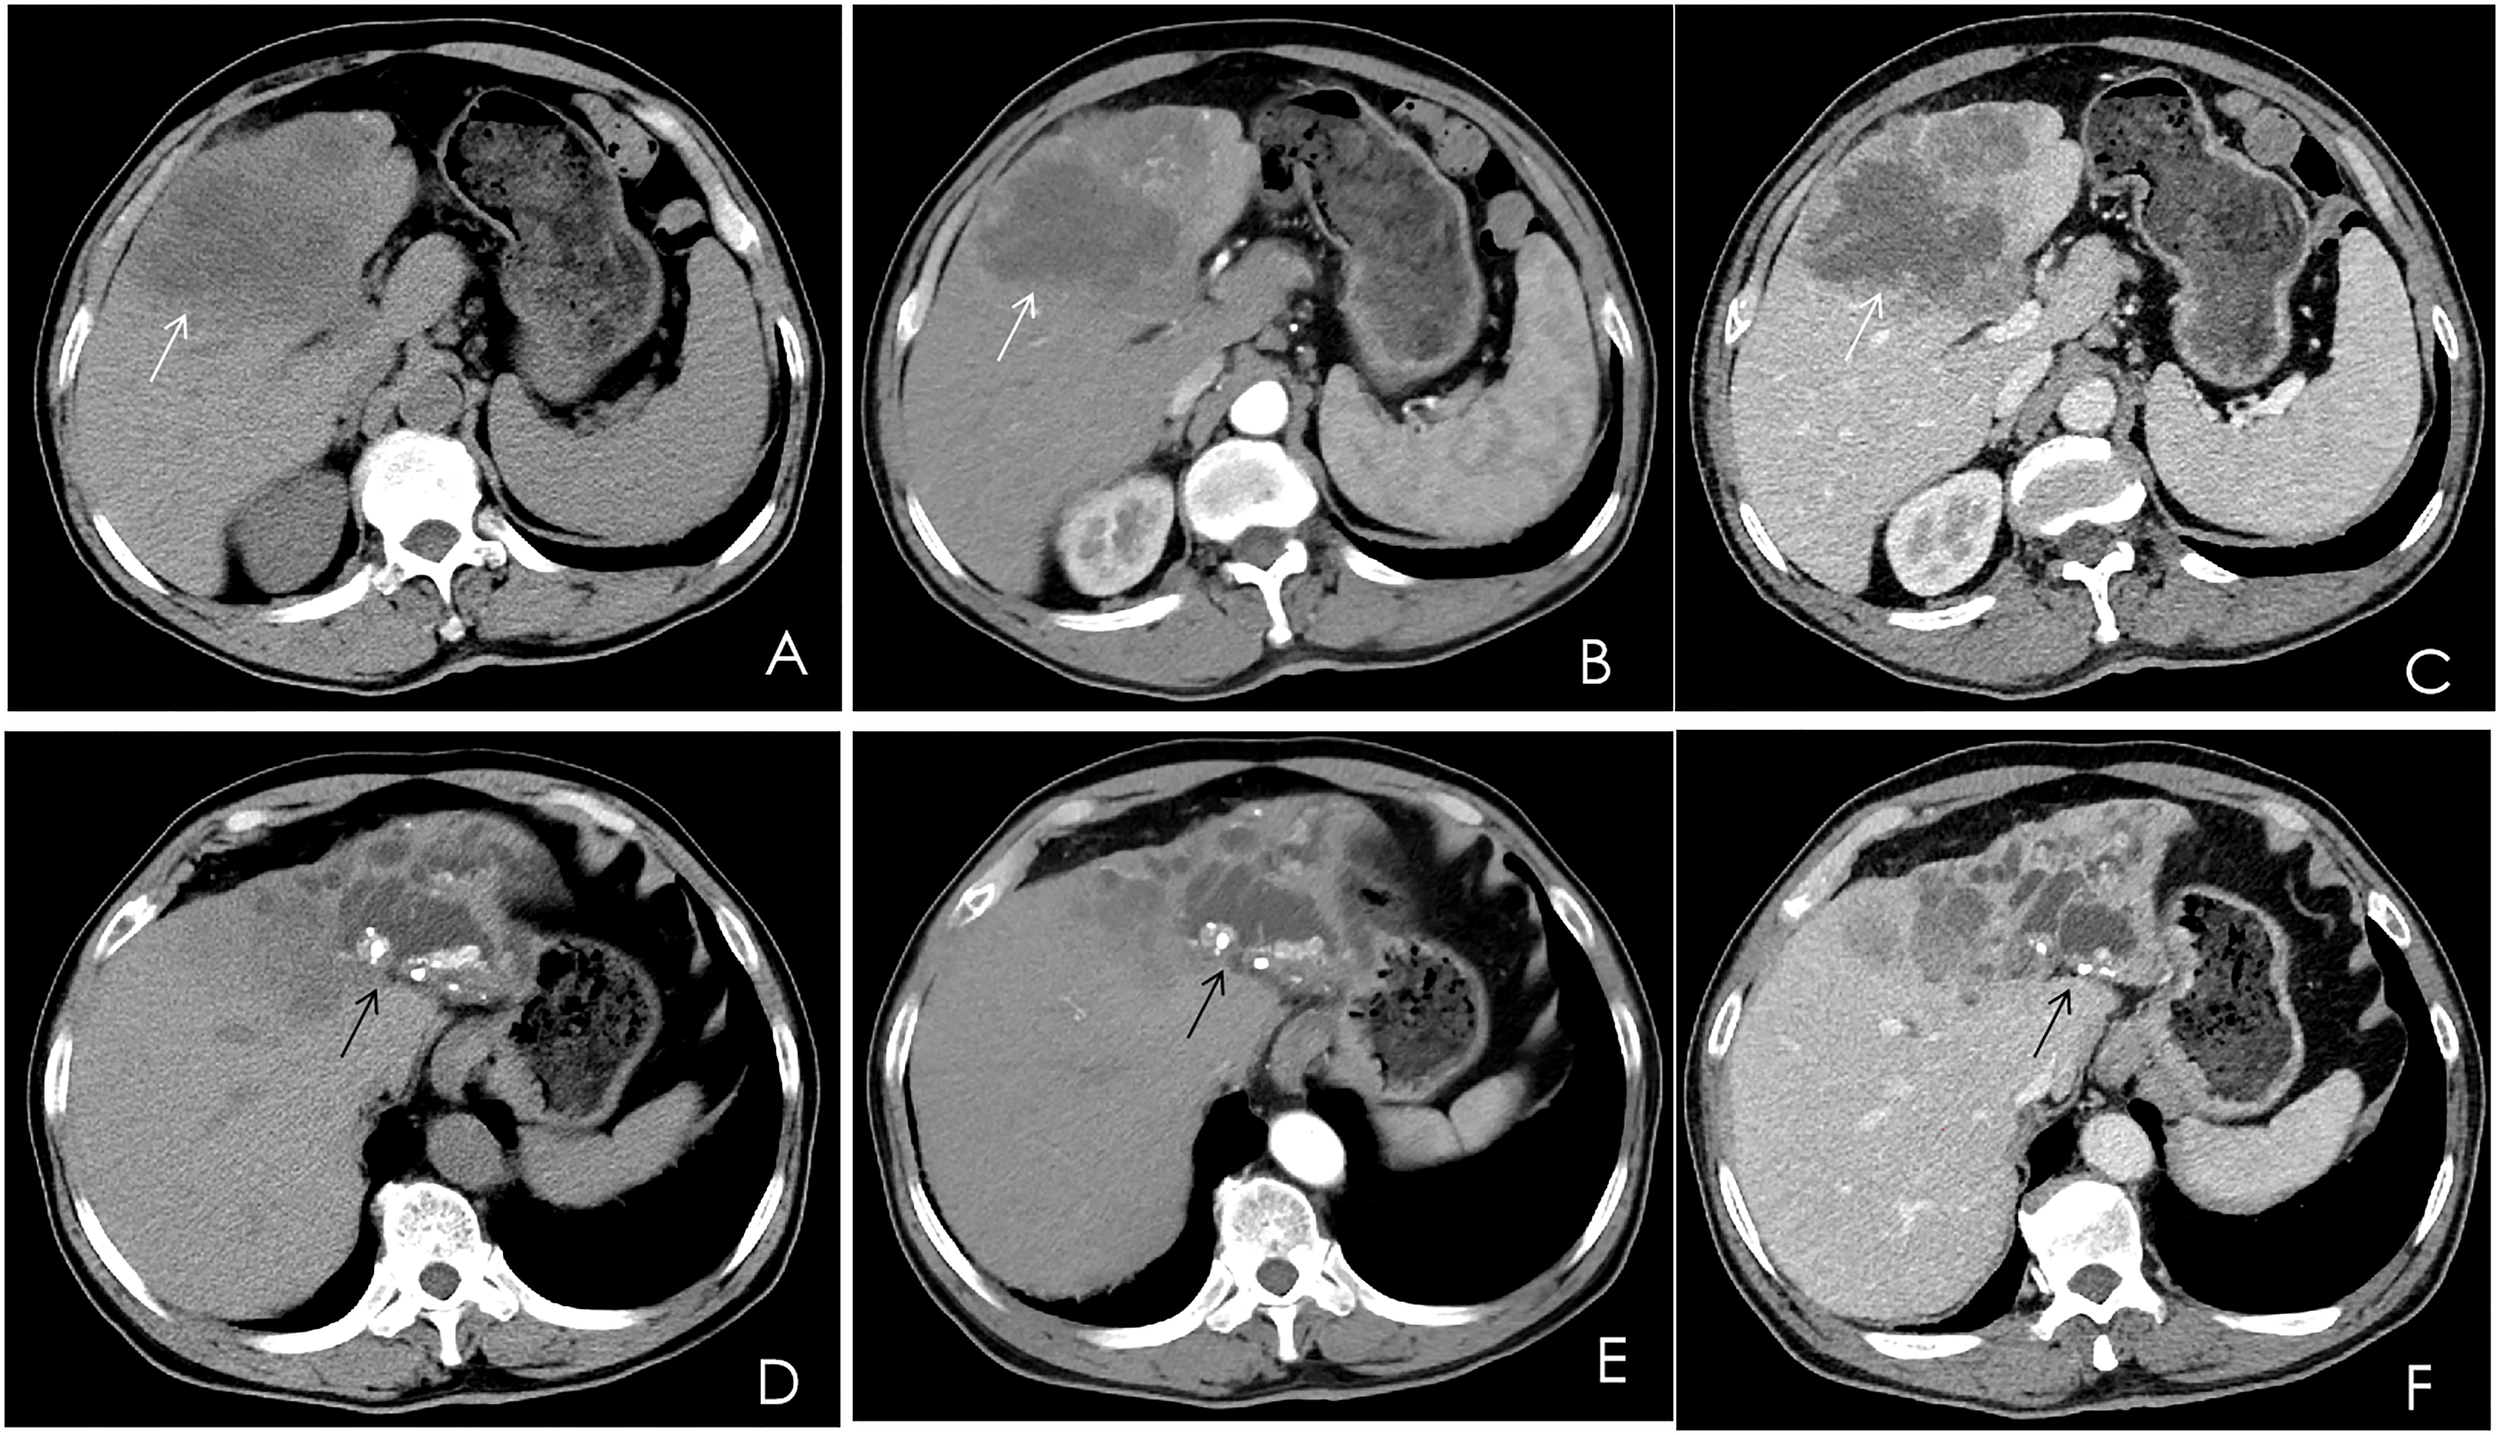

A contrast-enhanced computed tomography (CT) scan of the upper abdomen displayed multiple slightly low-density masses and mixed-density nodules in the left lobe and the anterior segment of the right lobe. The largest mass was measured at 11.2 × 8.5 cm from an axial view. Lesions showed ring enhancement in the arterial phase and continuous enhancement in the portal phase. The sagittal part of the portal vein was infiltrated. Dilatation of the left intrahepatic bile duct combined with bile duct stones was observed. In addition, there were enlarged lymph nodes in the hepatic portal, portacaval space, and around the abdominal aorta (Figure 1).

Multiphase contrast-enhanced CT of the upper abdomen, axial view. (A) A noncontrast CT showed multiple low-density masses and nodular mixed-density shadows in the left lobe and part of the anterior right lobe of the liver (white arrow). (B) The arterial phase showed heterogeneous ring enhancement (white arrow). (C) The venous phase showed continuous enhancement (white arrow). (D–F) The left branch of the intrahepatic bile duct and its branches were dilated, and high-density nodular shadows were seen in the liver (black arrow).